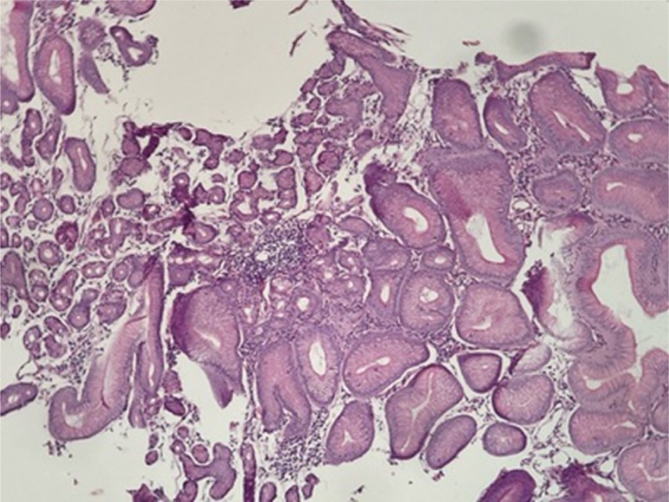

HETEROTOPIC GASTRIC MUCOSA OF THE ESOPHAGUS AS A POTENTIAL CAUSE OF PEPTIC STENOSIS AFTER ROUX-EN-Y GASTRIC BYPASS.

{"title":"HETEROTOPIC GASTRIC MUCOSA OF THE ESOPHAGUS AS A POTENTIAL CAUSE OF PEPTIC STENOSIS AFTER ROUX-EN-Y GASTRIC BYPASS.","authors":"João Victor Vecchi Ferri, Wagner Herbert Sobottka, José Alfredo Sadowski, Gustavo Rodrigues Alves Castro, Vitor Mamoru Haida, Marcela Scardua Cocicov, João Caetano Dallegrave Marchesini","doi":"10.1590/0102-6720202400055e1849","DOIUrl":null,"url":null,"abstract":"","PeriodicalId":72298,"journal":{"name":"Arquivos brasileiros de cirurgia digestiva : ABCD = Brazilian archives of digestive surgery","volume":"37 ","pages":"e1849"},"PeriodicalIF":1.8000,"publicationDate":"2025-01-20","publicationTypes":"Journal Article","fieldsOfStudy":null,"isOpenAccess":false,"openAccessPdf":"https://www.ncbi.nlm.nih.gov/pmc/articles/PMC11745473/pdf/","citationCount":"0","resultStr":null,"platform":"Semanticscholar","paperid":null,"PeriodicalName":"Arquivos brasileiros de cirurgia digestiva : ABCD = Brazilian archives of digestive surgery","FirstCategoryId":"1085","ListUrlMain":"https://doi.org/10.1590/0102-6720202400055e1849","RegionNum":0,"RegionCategory":null,"ArticlePicture":[],"TitleCN":null,"AbstractTextCN":null,"PMCID":null,"EPubDate":"2025/1/1 0:00:00","PubModel":"eCollection","JCR":"","JCRName":"","Score":null,"Total":0}